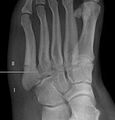

Cropped version of Jonesfracture.jpg

Jones fracture as seen on Xray

A Jones fracture is a break between the base and middle part of the fifth metatarsal of the foot.[8] It results in pain near the midportion of the foot on the outside.[2] There may also be bruising and difficulty walking.[3] Onset is generally sudden.[4]

The fracture typically occurs when the toes are pointed and the foot bends inwards.[6][2] This movement may occur when changing direction while the heel is off the ground such in dancing, tennis, or basketball.[9][10] Diagnosis is generally suspected based on symptoms and confirmed with X-rays.[3]

Diagnostic x-rays include anteroposterior, oblique, and lateral views and should be made with the foot in full flexion.